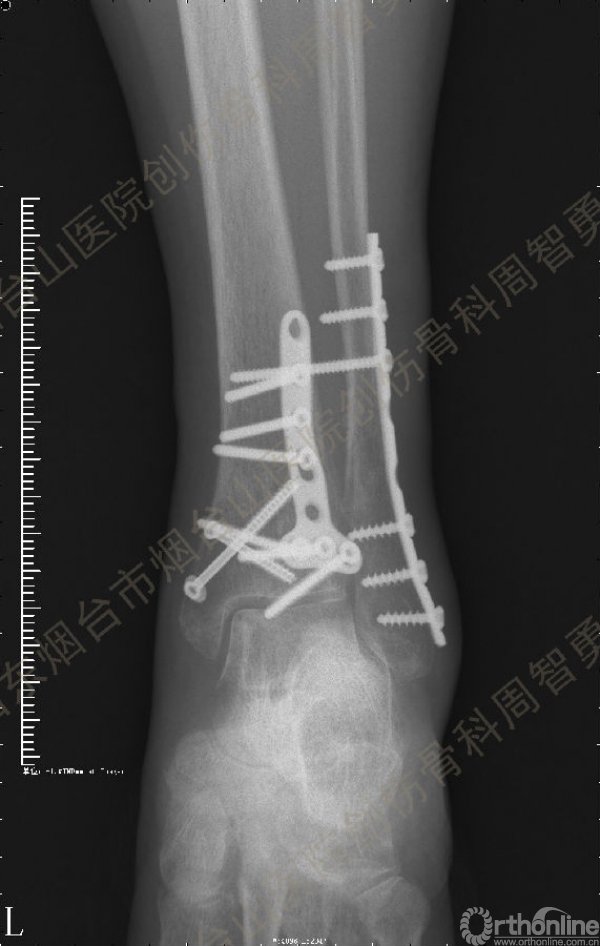

患者取俯卧位,轻度屈膝,小腿下垫枕使足离开床面。取长约10cm的踝关节后外侧切口,皮肤切口位于外踝后缘与跟腱的中线,远侧延伸至外踝尖。皮下与深筋膜间显露、保护小隐静脉和腓肠神经,纵向切开腓骨肌浅面深筋膜,显露腓骨肌腱。将腓骨肌腱牵向外侧显露后浅室和后深室间隔,透过肌间隔可见踇长屈肌。切开肌间隔显露踇长屈肌并向内侧牵开,显露胫骨远端后侧骨折块。保护腓动脉、下胫腓后韧带和骨折块上的骨膜。在后内侧骨折块和后外侧骨折块中间的骨折线切开骨膜并骨膜下游离数毫米,分别以胫后肌腱腱鞘和下胫腓后韧带为铰链,将后内侧骨折块和后外侧骨折块翻向内侧和外侧。显露后内侧骨折块腹侧向近端塌陷的骨软骨骨折块。见后内侧骨折块腹侧有约4.0 mm×3.0 mm×3.0 mm大小向近端塌陷的骨软骨骨折块,给予切除。取长约5cm的踝关节后内侧入路,切开皮肤皮下并适当向两侧游离,不切开屈肌支持带,仅切开后内侧骨折块内侧缘和近侧缘的骨膜。通过后外侧入路和后内侧入路显露后内侧骨折块的外侧缘、近侧缘和内侧缘,直视下解剖复位后,2.0 mm克氏针临时固定。直视下解剖复位后外侧骨折块,并用2.0 mm克氏针临时固定。返回后外侧切口,向外侧游离皮瓣,内牵腓骨长短肌腱显露外踝骨折,解剖复位后用2.0 mm克氏针临时固定。术中透视显示骨折块解剖复位。一枚4.0mm空心螺钉固定于后内侧骨折块的内上缘,另一枚4.0mm空心螺钉固定于后丘,5孔桡骨远端T型接骨板抗滑固定于后内侧骨折块和后外侧骨折块。8孔1/3管状板固定外踝骨折。术中Cotton试验阳性,复位下胫腓联合后,1枚3.5mm皮质骨螺钉固定。Chaput骨折块未作处理。术中及术后X线摄片示骨折解剖复位,内固定物位置正确。术后,踝关节于背伸0~5°,短腿石膏后托或支具固定2周。2周去除外固定开始踝关节主动功能练习。术后8周,X线片示骨折解剖复位,骨折线模糊,内固定物在位(图3a,b)。术后第11周开始部分负重,第13周拔除固定下胫腓联合的螺丝钉,逐步开始完全负重。术后4个月复查:X线片示骨折解剖复位,骨折线消失,内固定物在位;左侧踝关节主动背伸较健侧差10°,跖屈差10°;踝关节无疼痛,肌力较健侧无明显减退。

↑ 图 3a

↑ 图 3b

图 3 术后8周X线片示骨折解剖复位,骨折线模糊,内固定物在位